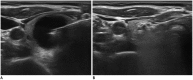

Minimally invasive treatment of symptomatic thyroid nodules is now commonplace. Ethanol ablation (EA) of thyroid cystic nodules has been performed since the 1990s, but there is no global consensus or guideline. Although various limitations of EA have been described, recommendations for practical application are necessary. Therefore, the Task Force Committee of the Korean Society of Thyroid Radiology initiated the present consensus statement and here we provide recommendations for the role of EA in the management of symptomatic thyroid nodules. These recommendations are based on evidence to date from the literature and expert opinion.